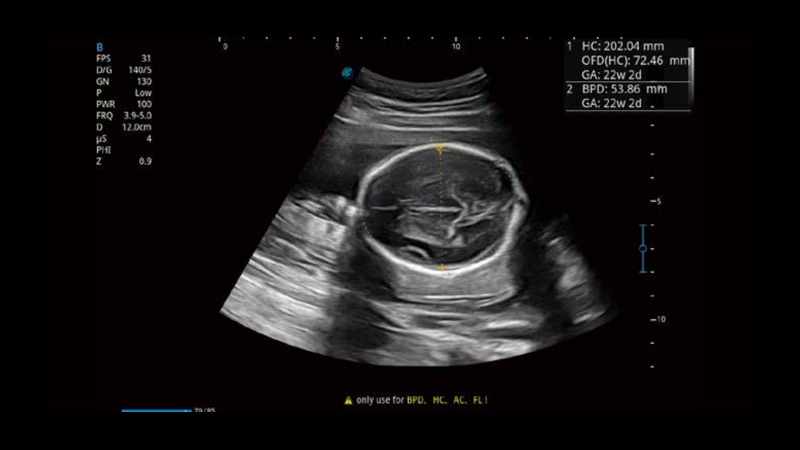

S-Fetus基于大數(shù)據(jù)深度學(xué)習(xí)算法,能夠幫助您在產(chǎn)前篩查過程中智能識(shí)別胎兒標(biāo)準(zhǔn)切面、自動(dòng)測(cè)量并錄入報(bào)告。一個(gè)按鍵,即可智能、精準(zhǔn)、高效地獲取胎兒生理指標(biāo),極大簡化您的產(chǎn)科檢查操作。

可快速對(duì)產(chǎn)科掃查切面完成胎兒生理學(xué)參數(shù)的自動(dòng)測(cè)量,減少操作者按鍵次數(shù),大幅提升檢查效率。

自動(dòng)識(shí)別頸項(xiàng)透明層并獲得NT值,為早孕胎兒畸形篩查提供有效測(cè)量工具,提高診斷效率和診斷信心。